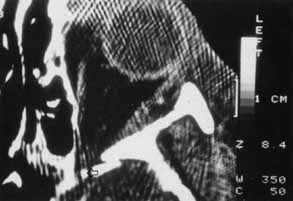

Hemorrhage can be localized to the subperiosteal potential space, extraconally, or intraconally within the orbital soft tissue, or within the belly of extraocular muscles. The condition can be associated with pain, nausea, diplopia, or decreased vision. The more obvious finding might be lid ecchymosis and edema but requires further examination for retroseptal signs. There may be conjunctival chemosis or expanding ecchymosis. Clinical findings reflect the mass effect of accumulating blood within the confines of the bony orbit and orbital septum (Fig. 2). Subperiosteal hematomas are usually restricted by the tight adherence of the periosteum to the orbital bone except in areas, such as suture sites, where this association is weakest. Hemorrhage localized to the muscle sheath may cause selective extraocular muscle restriction that requires radiologic studies to distinguish it from incarceration into a fracture site (Fig. 3). Localized bleeds within the orbital soft tissue can produce proptosis or dystopia. Diffuse hemorrhage may limit eye movement globally and increase retropulsive resistance. Increased intraorbital pressure on the globe and optic nerve may cause elevated intraocular pressure, choroidal folds, compressive retinal vascular compromise, or optic neuropathy, so maintaining vigilance for progressive, potential, vision-threatening situations is important.

Fig. 3 CT scan of inferior orbital hematoma (X) involving the inferior rectus muscle and causing severe upgaze and moderate downgaze limitation.